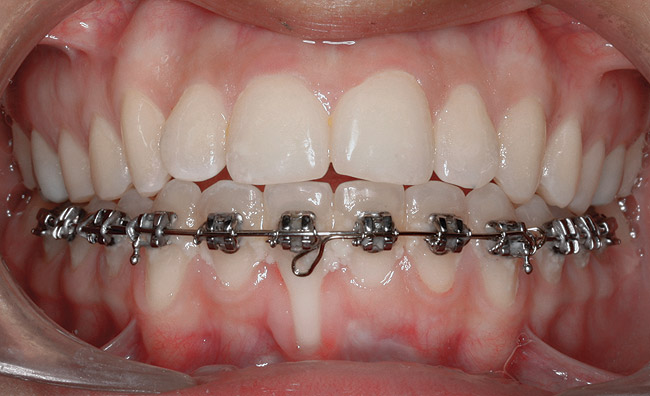

Case Report

A 19-year-old female complaining of gingival recession in the lower right central incisor presented to the authors’ clinic 5 years after completion of orthodontic treatment. The clinical evaluation showed Miller Class II GR accompanied by gingival inflammation (Figure 14). Two years later, despite conservative periodontal treatment, the GR had worsened (Figure 15). The occlusal view shows the presence of a fixed lingual retainer and a significant labial displacement of the root of the affected incisor (Figure 16 and Figure 17). At this stage, orthodontic treatment was considered. The patient was referred for CBCT, which showed no labial bone coverage of the root but 2.5 mm lingual bone thickness at 8 mm distance from the CEJ (Figure 18). After 6 months of orthodontic treatment with fixed appliances (Figure 19), the B-L inclination of the affected tooth was corrected (Figure 20). The frontal clinical view shows narrowing of the GR (Figure 21). Surgical coverage of the exposed root was subsequently performed by connective tissue graft (Figure 22). A long-term stable and esthetic result was achieved (Figure 23).

Fig 19. Frontal view showing the orthodontic appliance used in same patient.

Figure 19